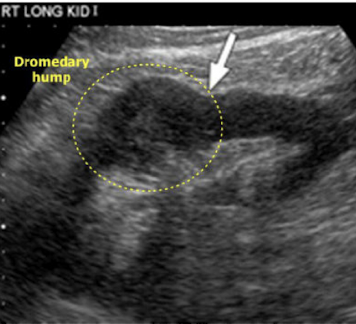

What anatomic variant is this and which kidney is it most commonly found in:

Dromedary hump: Most commonly found in the left kidney

What is this image showing:

Dromendary hump